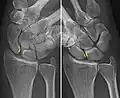

- Dynamic instability: Increased scapholunate distance (between yellow lines) upon ulnar deviation of the wrist, but not otherwise.